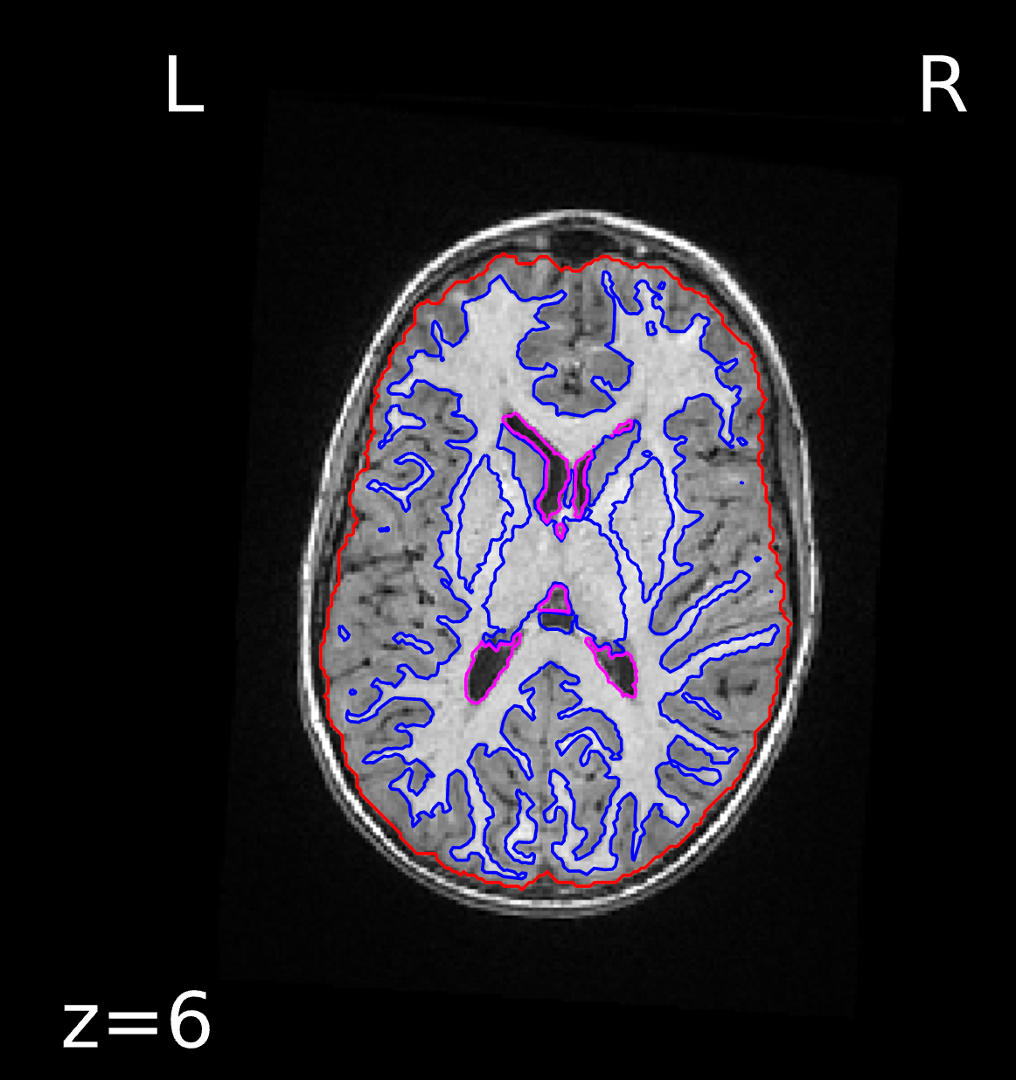

An example of output from the SCanD project preprocessing pipeline fMRI prep anatomical step is shown below for subject 3, a child without ADHD. Specifically, the image below shows the template T1-weighted image with contours delineating the detected brain mask (red outline) and brain tissue (blue outline) segmentations. These outputs were reviewed for quality assurance purposes.

Brain mask and tissue segmentation for subject 3, child without ADHD